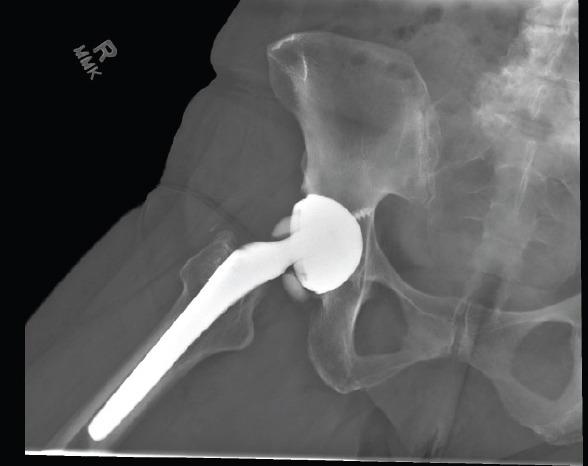

A 68-year-old Caucasian female presented with an atraumatic ceramic femoral head fracture in the setting of a ceramic-on-ceramic THA 17 years after primary surgery. The patient was successfully revised to a dual-mobility construct with a ceramic femoral head and a highly cross-linked polyethylene liner. The patient returned to normal function without pain.

The complication rate for fracture of the ceramic femoral head is as low as 0.001% for fourth-generation aluminum matrix composite designs, while the complication rate of late atraumatic ceramic fracture is largely unknown. We present this case to add to the current literature.